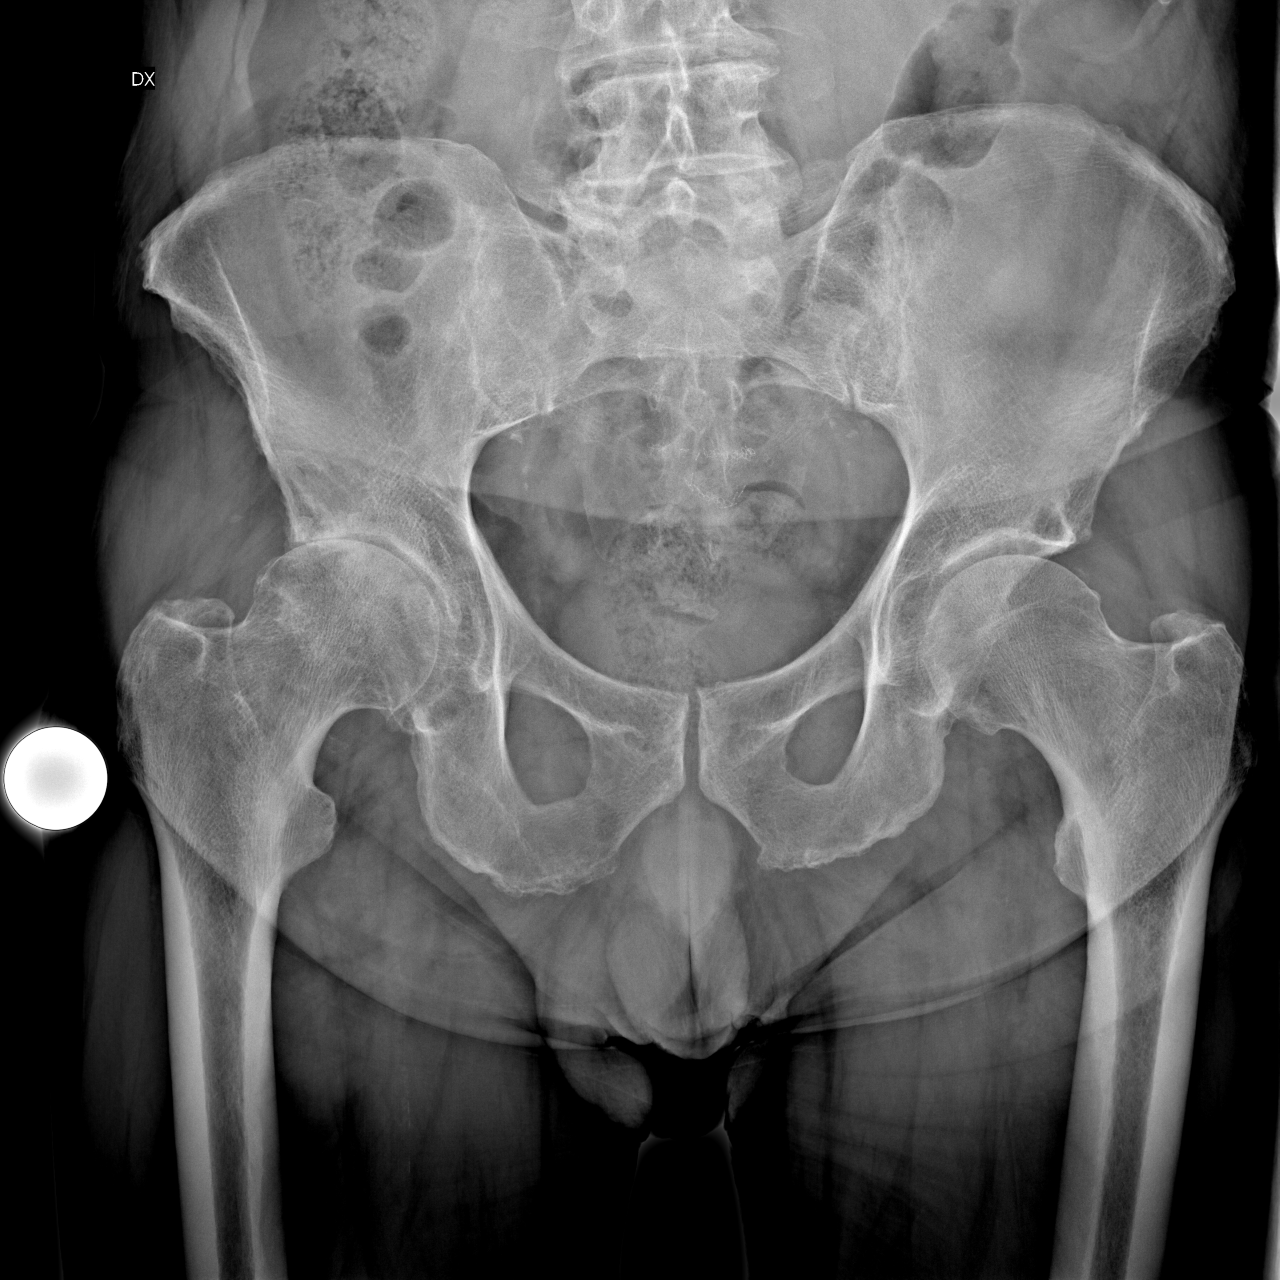

Il paziente che è stato candidato a questo tipo di intervento chirurgico era un paziente di anni 89, con pluripatologie in atto, cardiopatico con insufficienza cardiaca ed esiti di ictus cerebrale.

Presentava artrosi severa dell’anca destra che da alcuni anni impediva la deambulazione.

È stata impiantata una protesi modulare Microport.